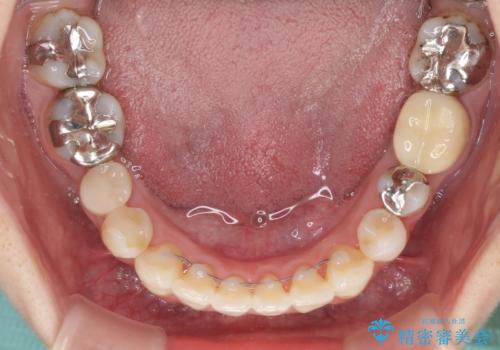

- 上下のデコボコと奥歯の咬みにくさを気にして来院された患者様です。

上顎骨の幅が下顎骨よりも小さいので、拡大装置により骨幅を広げて上下関係を改善し、その後インビザラインにて歯並びを整えることとしました。

上下の骨幅を改善したことで、スムーズに歯列矯正を行うことができました。

矯正治療中に近医で銀歯を外す治療を開始したため、治療後に奥歯の咬み合わせが不十分ですが(こちらは近医での治療により改善するとのこと)、歯列と咬み合わせが改善され、患者様には大変満足していただきました。